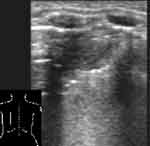

Плоская форма безвоздушного участка, когда в одном срезе он имеет размеры до нескольких см, а в перпендикулярной ему плоскости гораздо меньше, свидетельствует об ателектазе (Рис. 4, 5). При обширных безвоздушных участках на его присутствие указывает более острый конус безвоздушного сегмента, более высокое стояние края легкого, чем на противоположной стороне. В отличие от пневмонии в ателектазе не визуализируются эхогенные полоски содержащих воздух бронхов [7]. Исключение могут составлять крупные ателектазы у новорожденных, поскольку причина их возникновения не обструкция бронха, а нерасправление части легкого. Позади безвоздушных участков регистрируются усиленные эхосигналы.

[Увеличить]

Рис. 4. Небольшой ателектаз.

Рис. 5. То же, что на Рис. 4, во взаимно перпендикулярной плоскости.